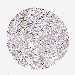

UROTHELIAL CANCER - Protein expressioni

A mouse-over function shows sample information and annotation data. Click on an image to view it in a full screen mode. Samples can be filtered based on level of antibody staining by selecting one or several of the following categories: high, medium, low and not detected. The assay and annotation is described here.

Antibody stainingi

Antibody staining in the annotated cell types in the current human tissue is reported as not detected, low, medium, or high, based on conventional immunohistochemistry profiling in selected tissues. This score is based on the combination of the staining intensity and fraction of stained cells.

Each image is clickable and will lead to virtual microscopy that enables deeper exploration of all samples and also displays staining intensity scores, fraction scores and subcellular localization as well as patient and tissue information for each sample.

Antibody HPA051132

Antibody CAB046473

Staining

High

Medium

Low

Not detected

Intensity

Strong

Moderate

Weak

Negative

Quantity

>75%

75%-25%

<25%

None

Location

Nuclear

Cytoplasmic/membranous

Cytoplasmic/membranous,nuclear

Urothelial carcinoma, High grade

Urothelial carcinoma, Low grade